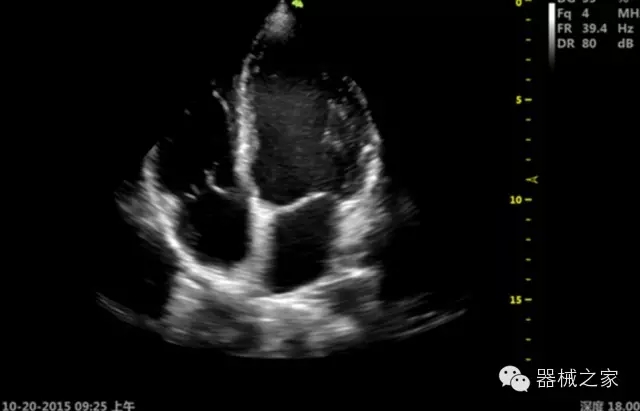

臨床圖片賞析

優(yōu)異的成像技術

·亞陣元技術:獨有的亞陣元技術,對獨立晶片做二次切割,減少旁瓣偽像,增加臨床診斷的準確性;

·μ-Scan微米成像技術:開立獨有的μ-Scan技術,還原出真實細膩、層次對比優(yōu)異的二維圖像;

·心功能綜合指數(shù)(TEI指數(shù)):用于左、右心室整體心臟收縮舒張功能評估的測量方法;

·全方位可調M型:有利于更好的觀察心腔大小及室壁階段性運動的異常情況;

·組織多普勒成像(TDI):TDI可定量評價心肌運動,判斷是否有局部病變,還可評價早期的舒張功能;